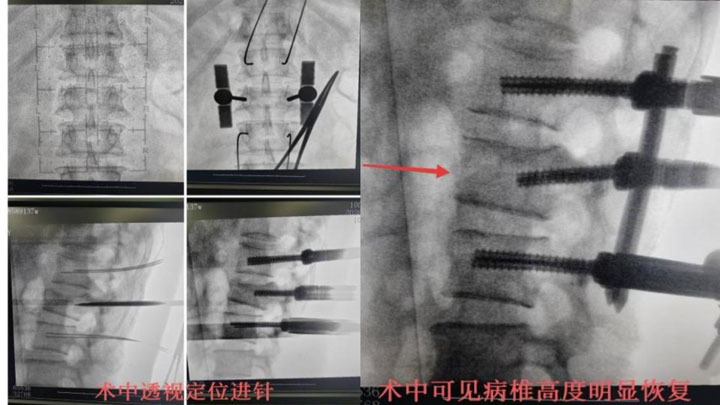

骨伤一科陈孝贵主任指出:根据患者病史、体征及影像学表现,患者腰椎压缩性骨折(L2 爆裂性)诊断明确,对于脊柱骨折保守治疗患者,需要长期卧床,极易出现褥疮、坠积性肺炎、下肢静脉血栓形成、肺栓赛等并发症,保守治疗椎高丢失会引起腰椎后凸畸形、慢性腰疼及继发腰椎不稳等后遗症,对于该患者,手术指针明确,手术目的:恢复椎高及清理椎管占位,促进早期下地,减少并发症及远期后遗症。建议患者行微创手术治疗方案-经皮椎弓根螺钉复位内固定术,患者及其家属同意并积极配合治疗方案,积极术前准备,在排除手术禁忌后,陈主任为其行手术治疗,手术顺利,术后2天即可佩戴支具下床活动。

微创治疗腰椎骨折能够最大程度保护肌肉韧带结构,避免了传统手术对腰背肌的切割、长时间牵拉和去神经化,这是术后慢性腰背痛显著减少的根本原因。同时,微创手术创伤小,出血少,疼痛轻,恢复快,感染风险更低。